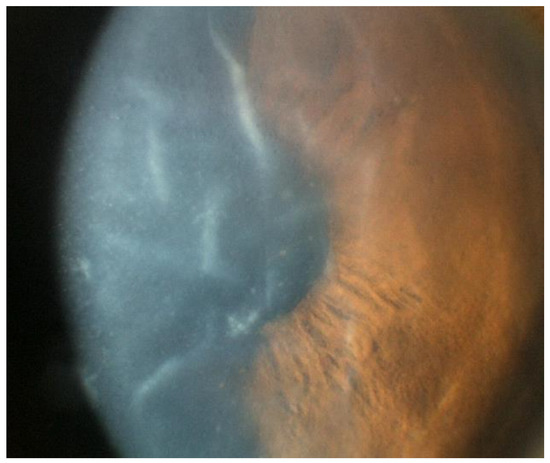

Unlike CMV, HSV endotheliitis occurs more commonly in individuals who are immunocompromised and in those with prior ocular infection [1]. Generally, HSV endotheliitis is caused by HSV-1, but HSV-2 may also be implicated [16]. Roughly one-third of HSV endotheliitis cases are bilateral, and like in CMV, a disciform pattern of KPs is most commonly found, although other configurations are possible (Figure 7) [19]. Similarly to CMV and VZV, overlying corneal edema may develop, severely limiting visual acuity (Figure 8) [19].

Figure 7.

Different patterns of keratic precipitates in viral endotheliitis. (a) Linear: fine KP (white arrow) in a linear pattern overlying corneal edema. (b) Sectoral: HSV endotheliitis with sectoral corneal edema (white arrows). (c) Disciform: a disciform pattern of KP (white arrow) with overlying corneal edema. (d) Diffuse: endotheliitis presenting with diffuse KP (white arrow) (Courtesy of Dr. Majid Moshirfar; used with the permission of the publisher [1]).

Figure 8.

Stromal edema due to HSV endotheliitis, with endothelial dysfunction in the absence of neovascularization and stromal inflammation (courtesy of EyeWiki; used with the permission of the publisher [21]).